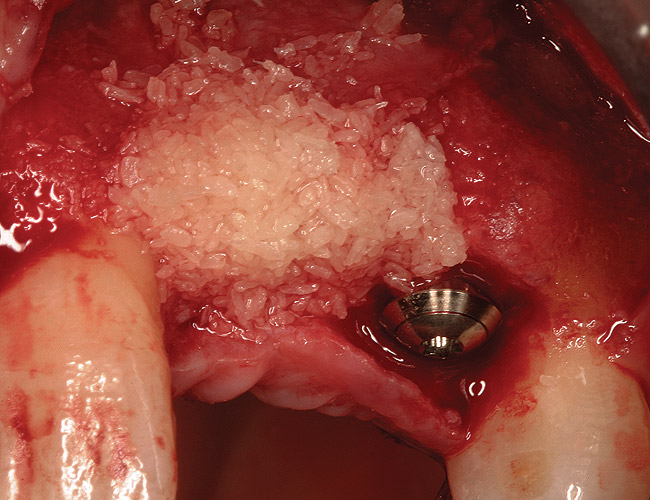

Figure 5  (Case 1) Site augmented with a combination of demineralized freeze-dried bone allograft, non-resorbable and resorbable barrier.

Figure 5

Figure 8  (Case 1) Additional augmentation with demineralized freeze-dried bone allograft at the time of implant placement.

Figure 8